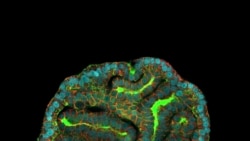

This microscope image provided by researchers in March 2024 shows a lung organoid created from cells collected from amniotic fluid. (Giuseppe Calà, Paolo De Coppi, Mattia Gerli via AP)